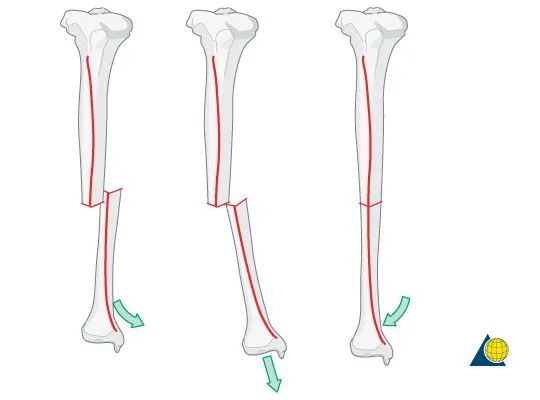

当胫骨轴正确对齐(“直线”)时,

小腿的形状略微弯曲,

向外凸出,内侧凹陷,与胫骨相对。

患者的外观应该类似。

如果患者看起来绝对笔直,

那么胫骨可能会再外翻。